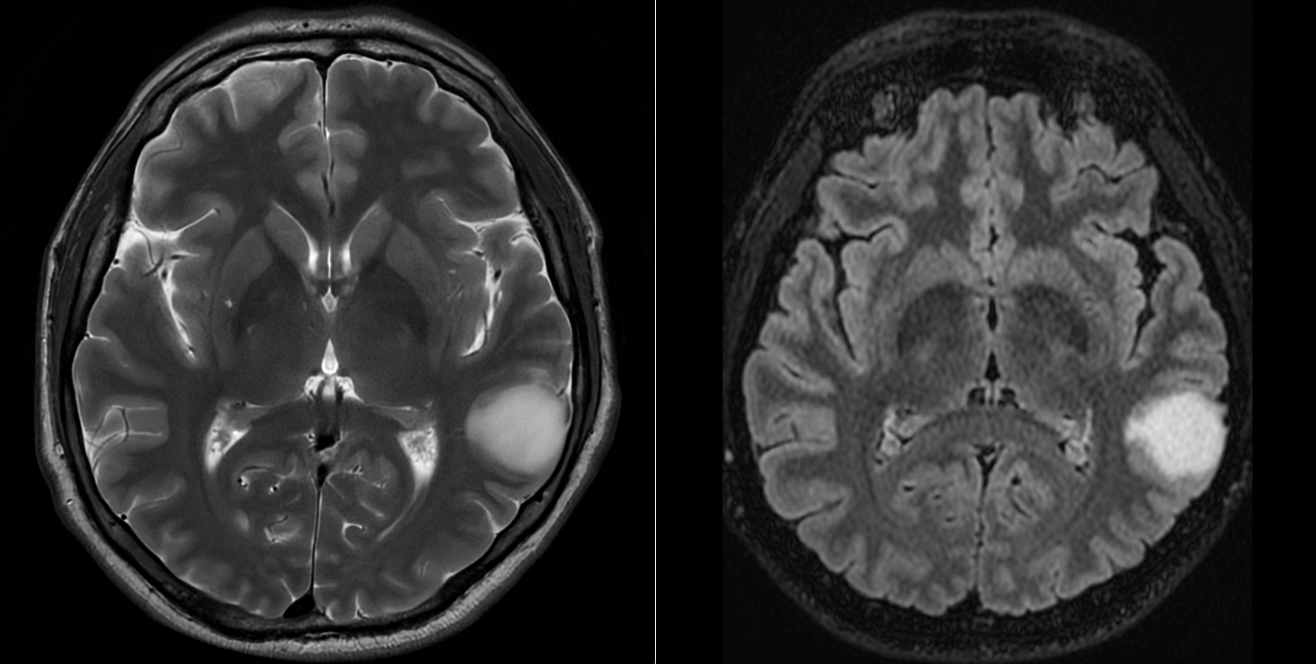

RMN-ul cerebral a evidențiat o tumoră temporală stângă cu semnal hiperintens în secvențele T2 și FLAIR, hiposemnal T1 și fără priză de contrast — un profil imagistic sugestiv pentru un gliom de grad mic.